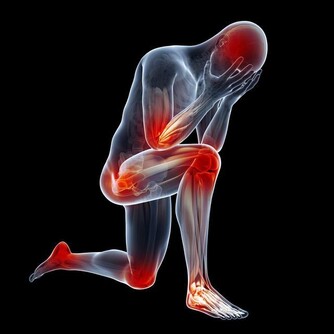

第一個信號:容易感到疲勞嗜睡,提不起精神當人體的免疫力下降時,身體里剩餘的免疫細胞就需要更多的力氣去做更多的工作。

所以這個時候,大腦為了減輕我們身體的負荷,所以你就會特別睏倦。